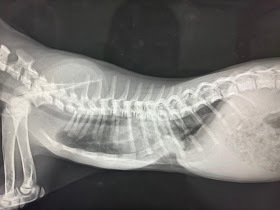

- ・漏斗胸

漏斗胸の例

生まれつき胸がへこんでいる子達がいます。 胸骨が曲がってしまっていて、肺の広がりが悪いので呼吸が苦しくなってしまう事があります。ギブスやプレートで骨の角度を変える手術が適応になります。